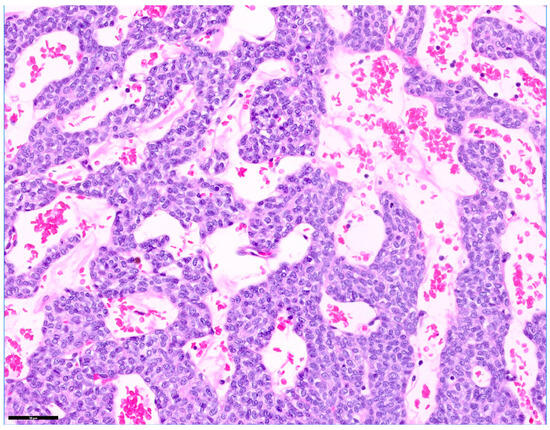

A 10-year-old castrated male Chihuahua weighing 3.06 kg was presented with a chronic, progressively worsening cough of five months’ duration. Diagnostic imaging, including thoracic radiography and computed tomography, identified a well-defined cranial mediastinal mass consistent with a thymic tumor. Surgical excision was performed via median sternotomy with complete thymectomy. Following tumor removal, sternal closure was achieved using a non-absorbable ultra-high-molecular-weight polyethylene (UHMWPE) suture material (FiberWire®, Arthrex, Naples, FL, USA). Histopathological examination confirmed the diagnosis of an epithelial-predominant thymoma with narrow but complete surgical margins. Postoperative recovery was uneventful, and the dog was discharged three days after surgery. Clinical signs, including coughing, progressively improved during follow-up. Radiographic evaluation performed up to postoperative day 57 demonstrated stable sternal alignment without evidence of dehiscence, implant-related complications, or disease recurrence. This report describes the first clinical case of FiberWire use for median sternotomy closure following thymectomy in a dog. The favorable clinical and radiographic outcomes observed during postoperative follow-up suggest that FiberWire may represent a viable alternative to traditional stainless-steel wire for sternal fixation in canine thoracic surgery. Full article